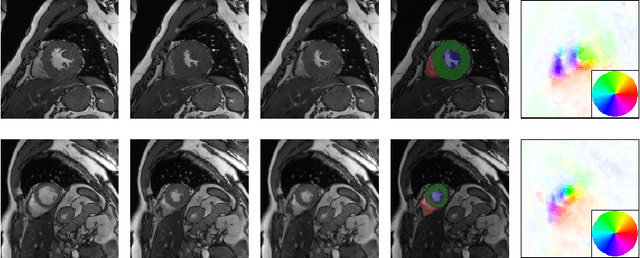

Cardiac motion estimation plays a key role in MRI cardiac feature tracking and function assessment such as myocardium strain. In this paper, we propose Motion Pyramid Networks, a novel deep learning-based approach for accurate and efficient cardiac motion estimation. We predict and fuse a pyramid of motion fields from multiple scales of feature representations to generate a more refined motion field. We then use a novel cyclic teacher-student training strategy to make the inference end-to-end and further improve the tracking performance. Our teacher model provides more accurate motion estimation as supervision through progressive motion compensations. Our student model learns from the teacher model to estimate motion in a single step while maintaining accuracy. The teacher-student knowledge distillation is performed in a cyclic way for a further performance boost. Our proposed method outperforms a strong baseline model on two public available clinical datasets significantly, evaluated by a variety of metrics and the inference time. New evaluation metrics are also proposed to represent errors in a clinically meaningful manner.